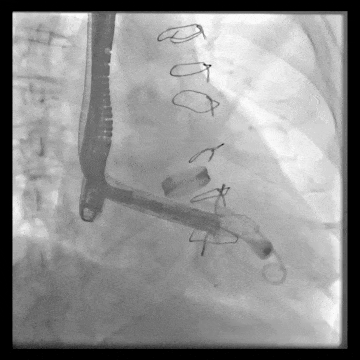

術中DSA顯示起搏器導線的干擾,右心室造影確定瓣環位置,操作空間小

術后DSA